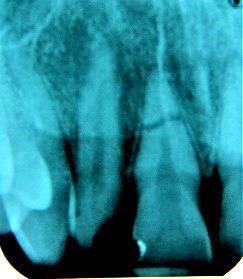

23-letni pacjent zgłosił się po urazie zęba 11 do gabinetu stomatologiczne- go. Obraz uzyskany w badaniu rtg zaprezentowano na załączonej rycinie. Na podstawie powyższych informacji wskaż optymalne postępowanie terapeutyczne: